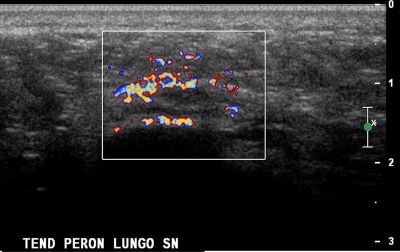

Tendinopatia del muscolo peroneo lungo tendine del m. peroneo lungo